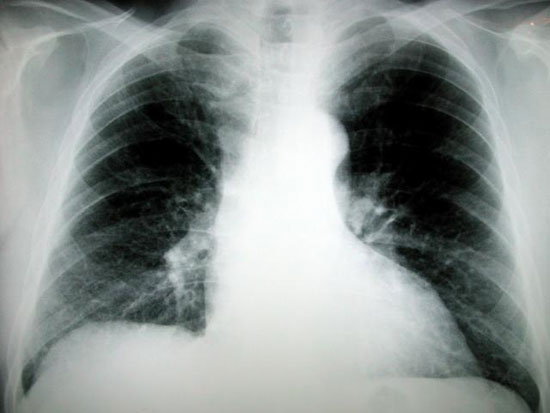

Trang medicalxpress ngày 8/9 đưa tin các bệnh nhân bị ung thư phổi giai đoạn cuối sắp được trang bị một công cụ điều trị nữa khi nhà chức trách y tế Cuba thông báo sắp tung ra vắcxin điều trị ung thư phổi đầu tiên trên thế giới.

Theo Tổ chức Y tế Thế giới, ung thư phổi là loại ung thư phổ biến và nguy hiểm nhất, khiến 1,4 triệu người trên thế giới tử vong mỗi năm.

Mặc dù những phương pháp điều trị hiện tại có thể nâng cao tỷ lệ sống cho bệnh nhân ung thư khi được phát hiện sớm, nhưng đối với những bệnh nhân bị ung thư phổi giai đoạn cuối thì tỷ lệ sống được 5 năm chỉ chưa đầy 1%.